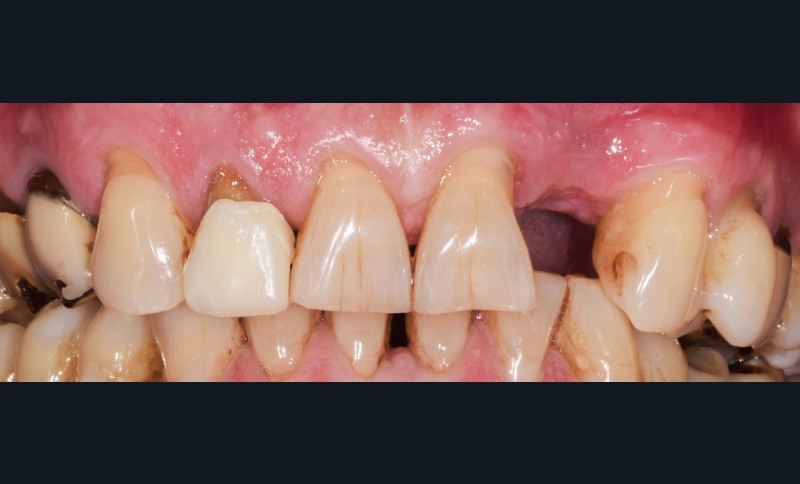

Situation initiale

Un patient de 62 ans se présente en consultation afin de réaliser les coiffes prothétiques des dents 12 et 22. La 12 présente une restauration par prothèse transitoire non adaptée. Un implant au niveau de la 22 a été posé par un autre praticien selon une technique chirurgicale en deux temps. Le praticien a adressé le patient pour la réalisation prothétique. L’option de bridge collé cantilever mono ailette n’avait pas été retenue ou proposée selon une technique chirurgicale en deux temps. Le patient souhaite rétablir l’esthétique et la fonction de ces deux dents uniquement.

Au vu des conditions initiales, il nous apparaît impossible de restaurer une esthétique satisfaisante, notamment au niveau de l’alignement des collets, sans une chirurgie muco-gingivale associée à une réhabilitation des dents antérieures par facettes. En effet, la perte de la 22, associée à une forme triangulaire des dents, a provoqué un non-alignement des collets ainsi que la présence de trous noirs entre les dents 21-22 et 22-23. Cependant, les contraintes exprimées par le patient contre-indiquaient ce traitement.